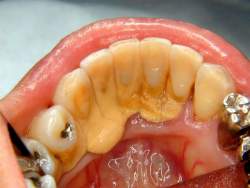

歯石除去スレ

どうせならこの位溜めてから行きたいよね

そこまで溜めたら歯槽膿漏で歯が…

歯石もだが金属冠多用してる時点で・・・

銀歯いれてるのにさらにここまでたまるってことは相当できやすい体質だな

親の教育か

18無念Nameとしあき26/03/23(月)12:27:36No.1395809238+

歯石で歯を支えてるようなの好き

スレ画はいいサンプルでは

歯茎が下がって歯の根本が見えてる